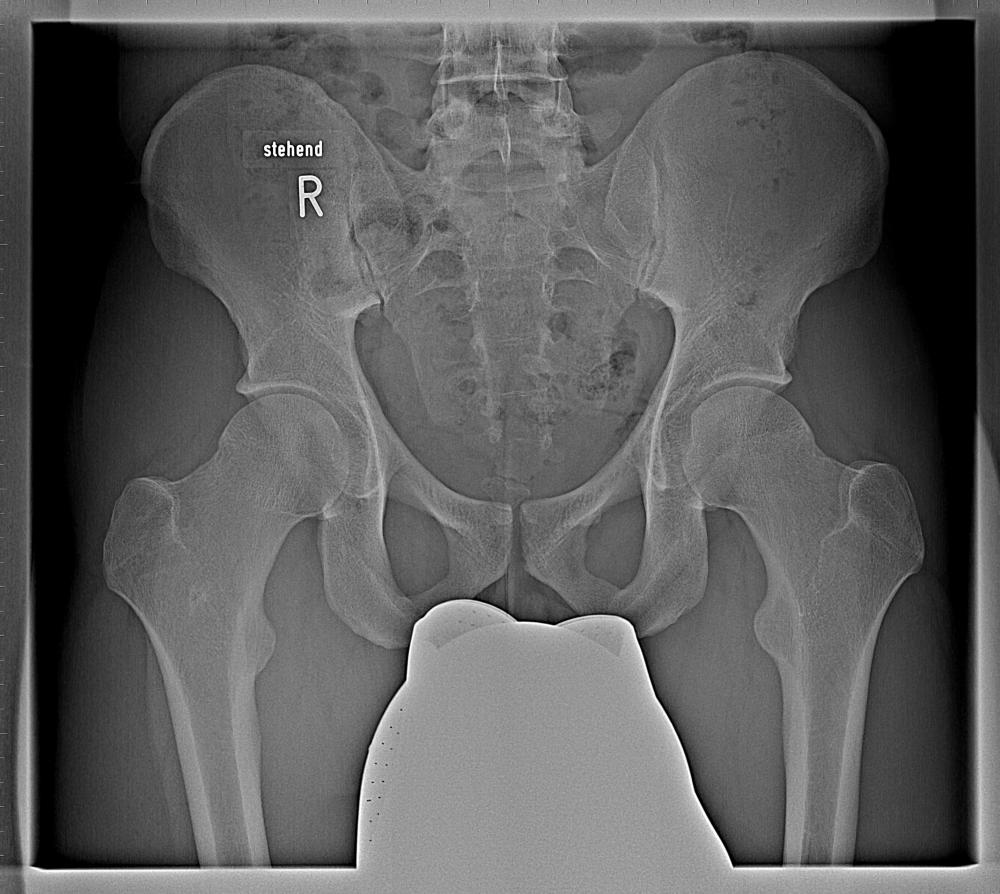

ich brauche mal euren Rat. Bei mir wurde eine leichte Hüftdyplasie festgestellt. Da ich Orthopäden nicht so recht traue möchte ich euch bitten, dass Bild zu beurteilen.

Was man auf dem Bild gut sehen kann, ist keine klassische Hüftdysplasie (zu flach ausgeprägte Pfannen) sondern eher zu stark ausgeprägte bzw. deutlich vertiefte Hüftpfannen, das ist eine Form des "Femoroacetabuläres Impingement" (FAI). In deinem Fall wäre das das "Pincer-Impingement". Bei diesem "Beißzangen-Impingement" ist meist die Hüftpfanne deutlich vertieft, die Hüftkopfform jedoch normal. Dadurch stößt der Schenkelhals wiederholt am Pfannenrand an und verdrängt oder klemmt die Gelenklippe ein und schädigt sie mit der Zeit. Typisch hierfür sind Leistenschmerzen bei bestimmten Bewegungen. Diese lassen sich bei einem Befund gut reproduzieren!

Um auf Nummer sicher zu gehen würde ich vielleicht noch ein MRT machen lassen. Dadurch lassen sich evtl. Schädigungen der Gelenkslippe gut erkennen.

Was mir noch aufgefallen ist, ist dass dein Steißbein etwas verschoben/subluxiert ist. Hast du manchmal Taubheitsgefühle oder Kraftlosigkeit in den Beinen?

@Stephan Ich bin männlich und 27 Jahre alt. Der Orthopäde selbst möchte nicht tun. Er hat mir eine Heilmittelverordnung ausgestellt und folgendes ist dort vermerkt:

Diagnose: Leichte Hüftdysplasie, Funktionsstörungen durch Muskeldysbalance, - Insuffizienz, -verkürzung

Therapie: Wiederherstellung, Besserung der gestörten Muskelfunktion, Muskelaufbau, Kräftigung der Hüftabduktoren und Außenrotatoren, Anleitung zum Eigentraining

würde sagen, keine Probleme mit der Hüfte, aber Gleitwirbel/ Abnutzung Wirbelfortsätze, Problem ISG (links auf dem Bild).

Das rauhe Sitzbein kann ggf. auf Überlastung der Sehnen, Anfälligkeit der Sehnen/ Schwache Sehnen hinweisen, muß aber nicht.